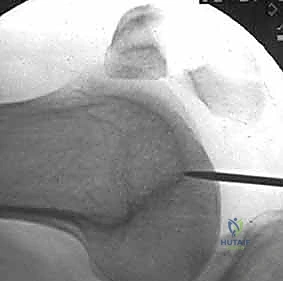

Retrograde femoral nailing can be defined as any femoral nailing technique with a distal entry from the condyles or through an intercondylar, intra-articular starting point. For this chapter,retrograde femoral nailing will refer to nails with an intercondylar starting point that extend through the shaft region to the proximal femur. In certain fracture situations, shortened nails (supracondylar nails) can be used with the same starting point for fixation of distal femoral fractures. ## ANATOMY The femoral shaft is tubular in shape over the extent of the isthmus, gradually flaring infraisthmally into the distal femur, which is trapezoidal in cross-section. The entry point for the retrograde femoral nail is located at the distal end of the patellofemoral grove, just anterior to the posterior cruciate ligament insertion ( FIG 1A). Radiographically, this is located in the midline or just medial to the midline between the condyles on the anteroposterior (AP) view and laterally just anterior to the line of Blumensaat as it meets the trochlear grove ( FIG 1B,C).5, 12, 14, 15, 18 This flat articular area has minimal to no contact with the patella until 120 degrees of flexion. 1, 5

### FIG 1 • A. Distal femur viewed end on, with ideal starting point for retrograde femoral nailing identified (asterisk) just anterior to the posterior cruciate ligament insertion. B,C. AP and lateral radiographs of the knee, with the initial starting guidewire positioned at the ideal starting point for retrograde femoral nailing. The radiographic landmark for the trochlear groove (TG) is indicated on the AP radiograph and for the line of Blumensaat (BL) on the lateral radiograph. Pertinent proximal anatomy includes neurovascular structures anterior to the proximal femur, close to interlocking screw insertion sites. 24 The femoral artery is medial to the proximal femur, with branches that cross the anterior femur more than 4 cm distal to the lesser trochanter. Branches of the femoral nerve cross more proximal starting 4 cm distal to the piriformis fossa. Damage to neurovascular structures caused by proximal locking screw insertion can be avoided or minimized by avoiding medial dissection and with placement at or above the lesser trochanter ( FIG 2). ## PATHOGENESIS Femoral shaft fractures are markers of high-energy injuries. 10, 12, 13, 14, 23, 27 Studies have shown that 38% of trauma patients diagnosed with a femoral shaft fracture have additional injuries. 3, 7, 8, 26 In femur fracture patients with associated injuries, the most common findings are other musculoskeletal injuries (93%), thoracic injuries (62%), head injuries (59%), abdominal injuries (35%), and facial injuries (16%). 7